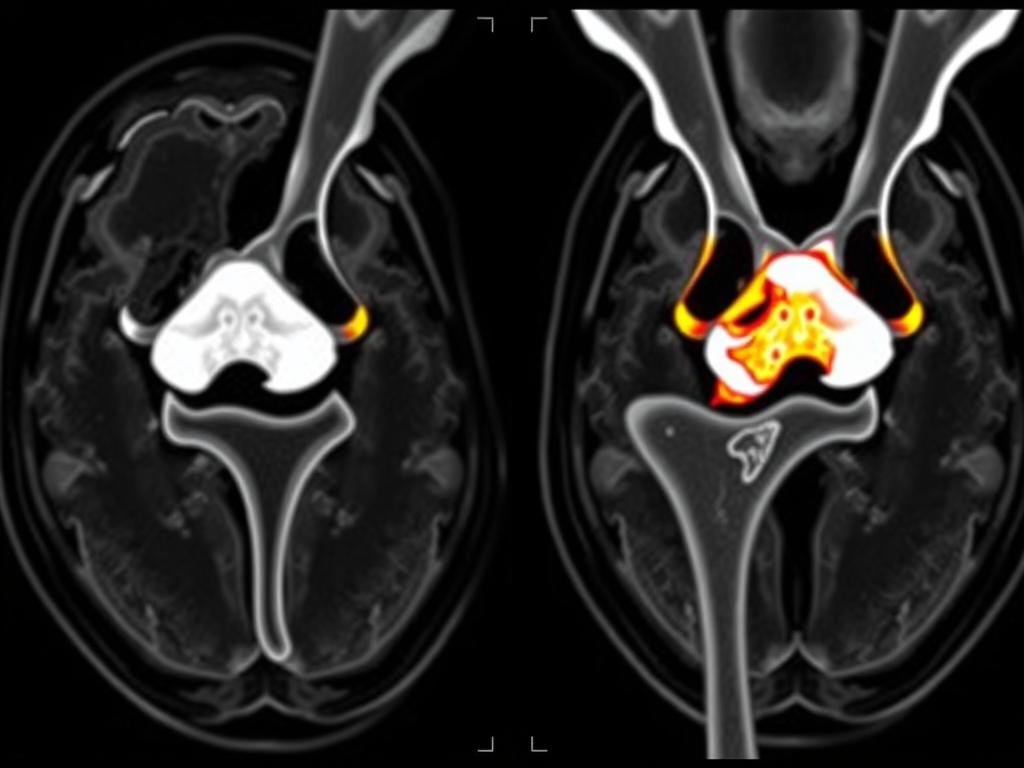

- Magnetresonanztomographie (MRT): Ermöglicht eine detaillierte Darstellung der Weichteilstrukturen und ist besonders gut geeignet, um Kreuzbandrisse zu erkennen

MRT-Bild eines gerissenen vorderen Kreuzbandes